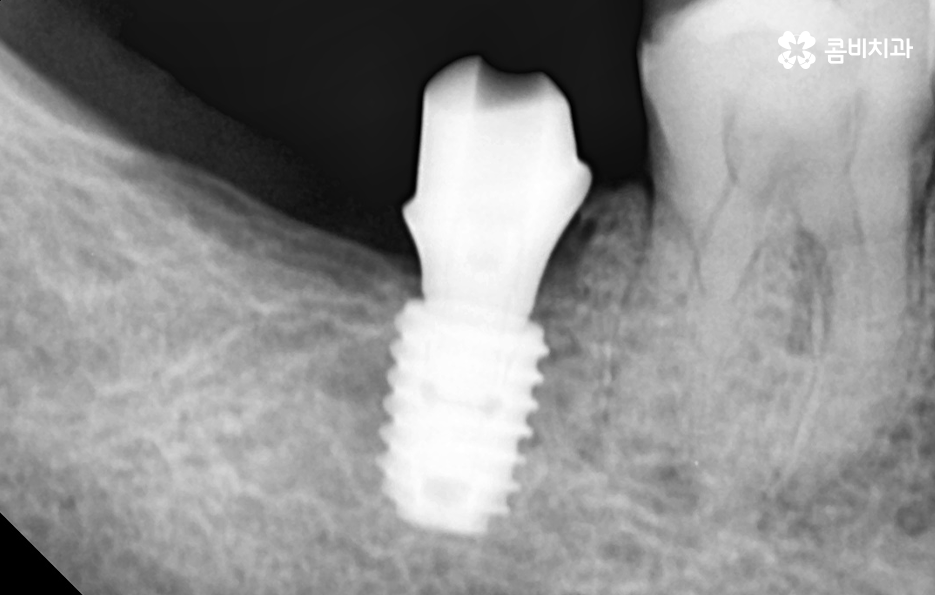

임플란트 치료의 성공 여부는 임플란트가 잇몸 뼈에 안정적으로 골유착이 진행되고 튼튼하게 고정되어 있어야 하기 때문에 치료 전에도 잇몸 건강이 중요하지만 치료 후에도 잇몸 건강이 관건이라 할 수 있는데요

어금니 임플란트 치료를 잘 받았다면 그 이후에는 얼마나 수명 유지를 잘하는지에 따라서 10년이상 건강하게 사용할 수도 있고 반대로 제대로 관리하지 않는다면 임플란트의 수명도 줄어들고 임플란트 주위염 등으로 고생하는 사례도 많이 있어요